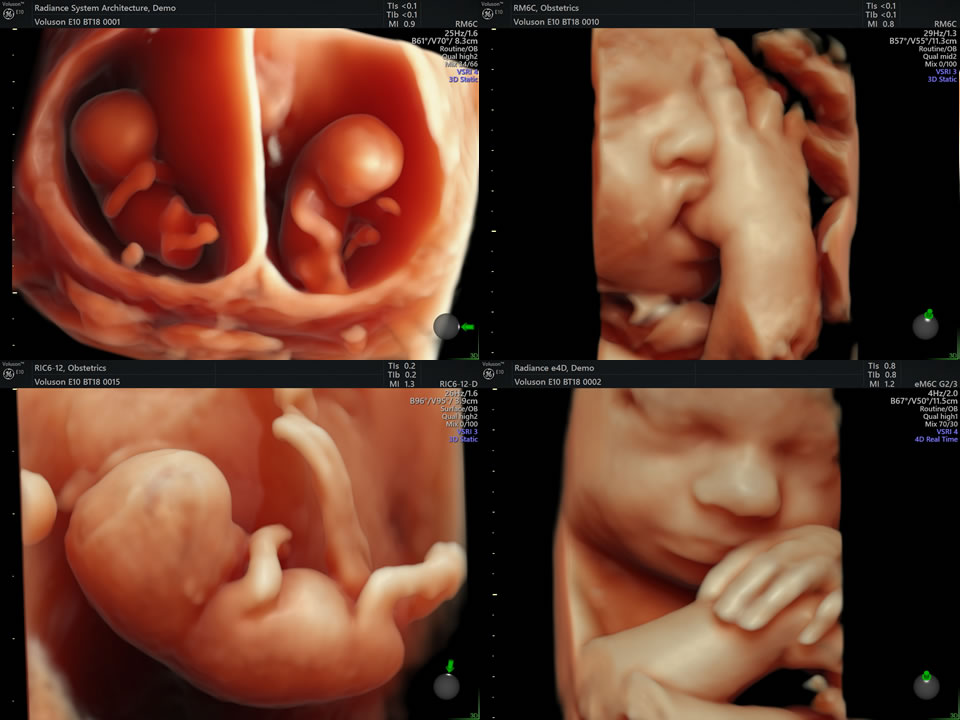

Ultrassonografia Obstétrica 3D | 4D | 5D Essa ultrassonografia oferece uma experiência mais imersiva e detalhada da gestação.

🔹 Diferenças:

3D: Imagem estática do bebê em alta definição.

✅ 4D: Imagem em movimento, mostrando expressões e movimentos do feto.

✅ 5D: Tecnologia avançada que proporciona imagens mais realistas e com melhor definição.

Além de proporcionar um vínculo emocional incrível, esse exame permite observar com mais detalhes a anatomia do bebê.